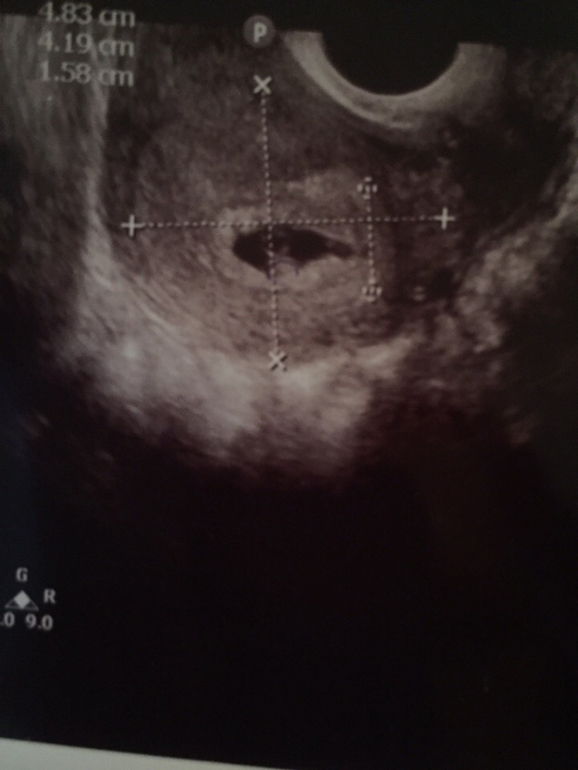

Беременность первая, в 6 недель я ходила на УЗИ, просто чтобы подтвердить маточную беременность. Но врач немного посмотрев, сказала, что возможно их там 2. Она сказала, что одного точно видит, а второй пока не на 100%, но пузырек увидела. Ни про сердцебиение, ни про желтый мешочек, ничего не говорила. А я как то и расстерялась, да и не знала, что вообще спрашивают в таких случаях. Сказала повторить узи через две недели, но время тянется безумно долго. У моего отца есть братья(только я не уверена, близнецы или двойня, не общаемся давно) + у отца парня тоже должны были быть братья близнецы, но закончилось печально. Получается, что шанс есть?Решила спросить тут:)Может кто-то сталкивался с таким, или хоть немного разбирается в снимках:)

P.S один пузырек определился на срок 6недель и 1 день, второй на 5 недель и 6 дней. Там на двух последних снимках будет написано наверху слева, а так же размер пузырьков)

P.S.S Если не ошибаюсь, она сказала что тот, что 5недель и 6 дней и есть эмбрион, но что тогда может быть тот, что на 6недель+1?я окончательно запуталась😢